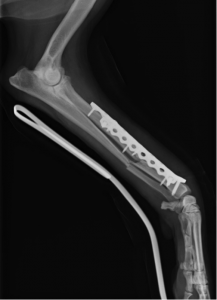

術後レントゲン

コメント;

短い遠位骨片にはφ2.7mmのコルチカルスクリュー1本とφ4.0mmのロッキングスクリュー2本を使用しました。KYON社のALPSプレートはその形状からプレートを並列した場合、骨に対するプレートの幅を他のDCPプレートなどと比較して最小限にすることが可能でありダブルプレートを実施する場合には非常に有効と思われます。